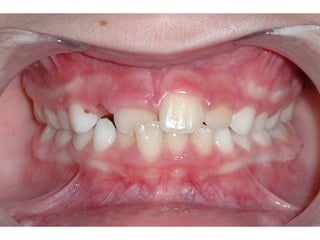

Πρώτη σχολική ηλικία 6-10 ετών

   Αρχίζει αλλαγή των τομέων και η ανατολή των

πρώτων μόνιμων γομφίων (μεικτή οδοντοφυΐα)

   Παρατηρούμε η αλλαγή δοντιών να γίνεται με τη

σωστή σειρά και στη σωστή θέση

   Μπορεί να χρειαστεί πρώιμη ορθοδοντική

θεραπεία, για να αποφευχθούν πιο δύσκολες και

πολύπλοκες εργασίες αργότερα

   Διατήρηση νεογιλών δοντιών στον οδοντικό

φραγμό μέχρι τη φυσιολογική τους απόπτωση